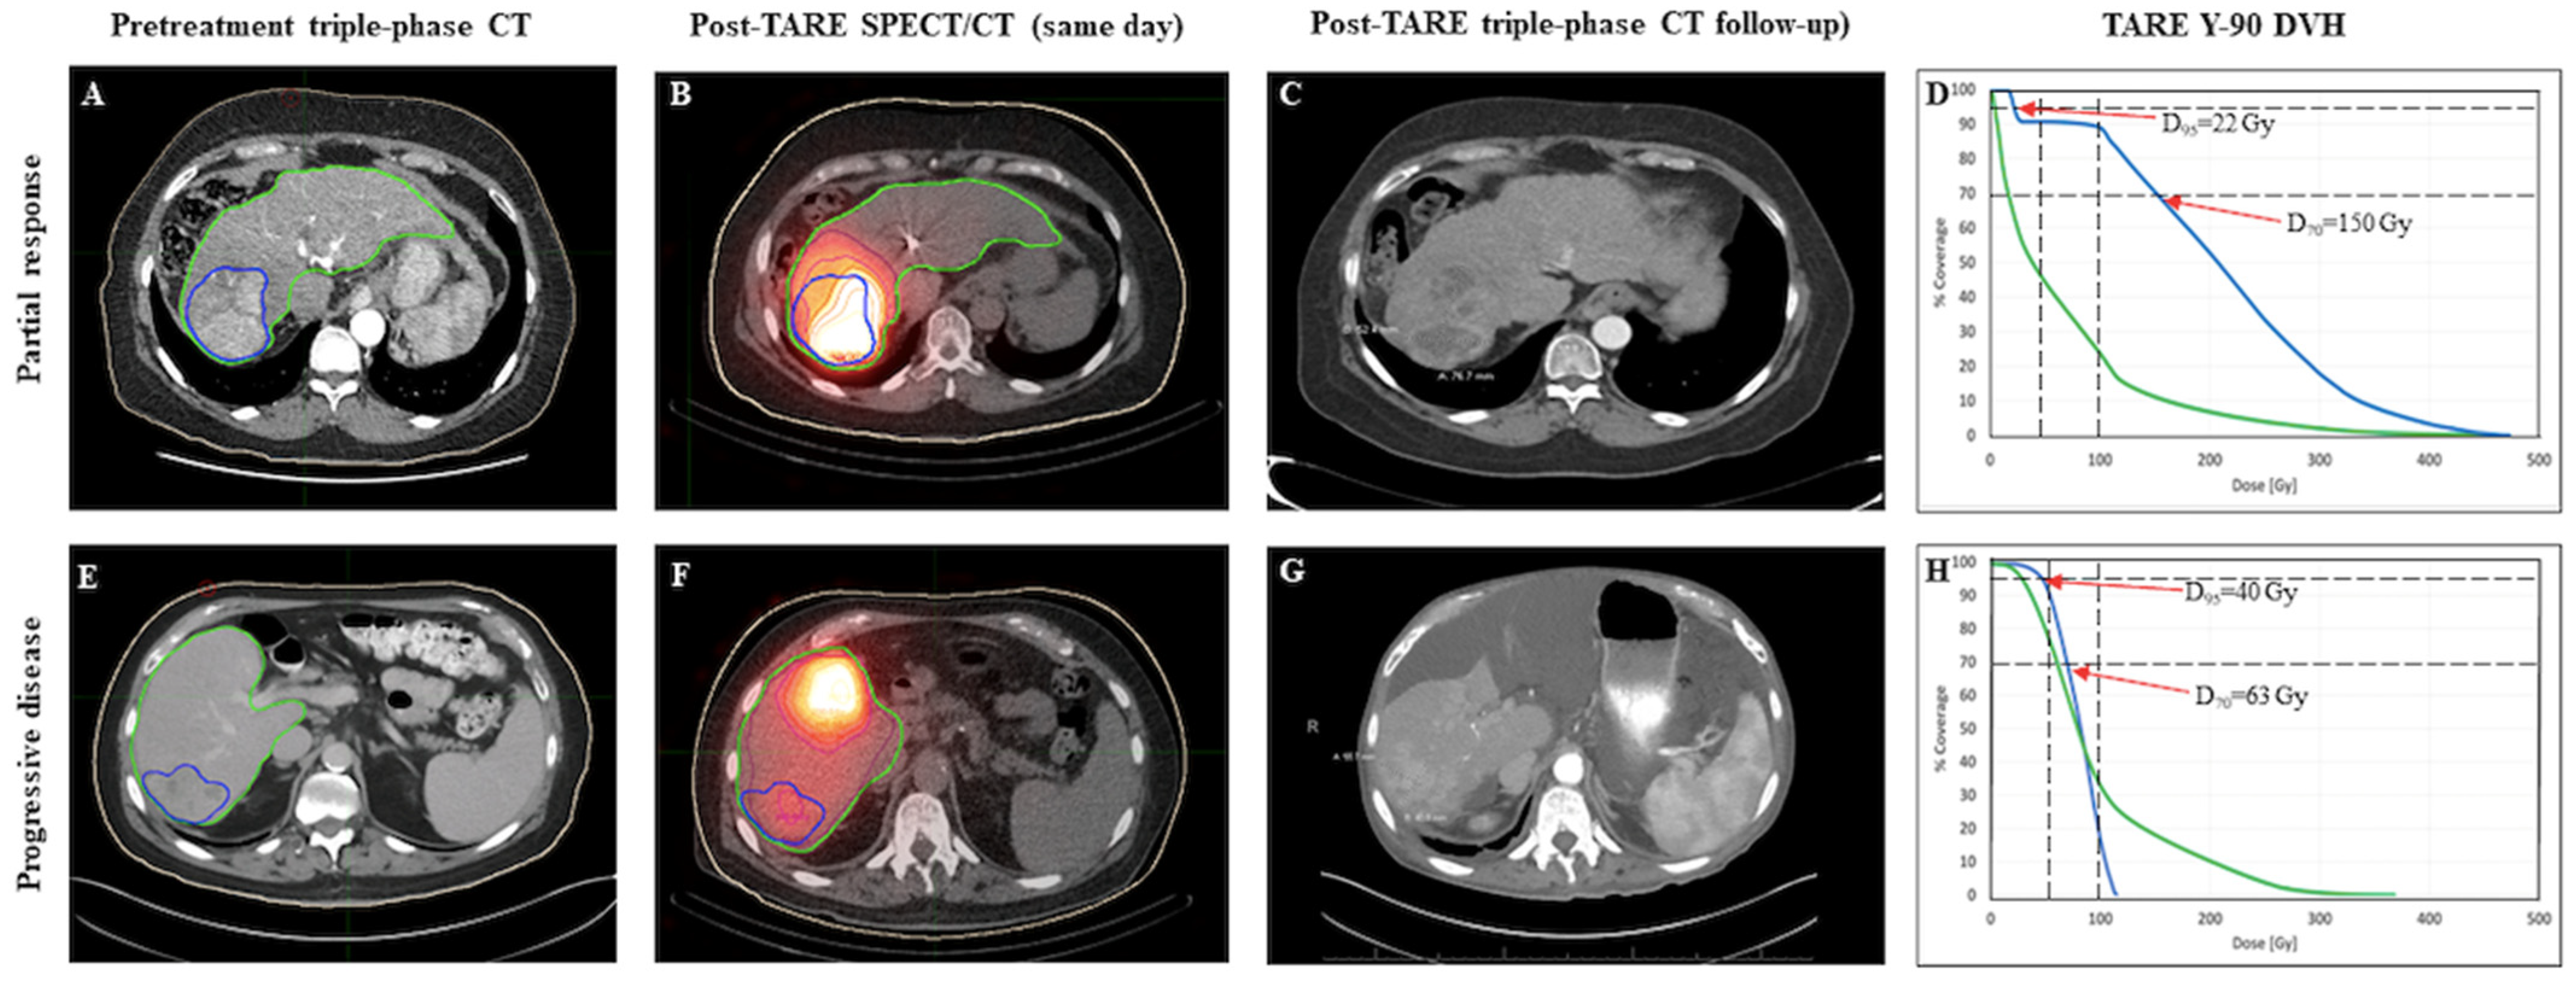

2.3. Post-Treatment 3D Advanced Dosimetry